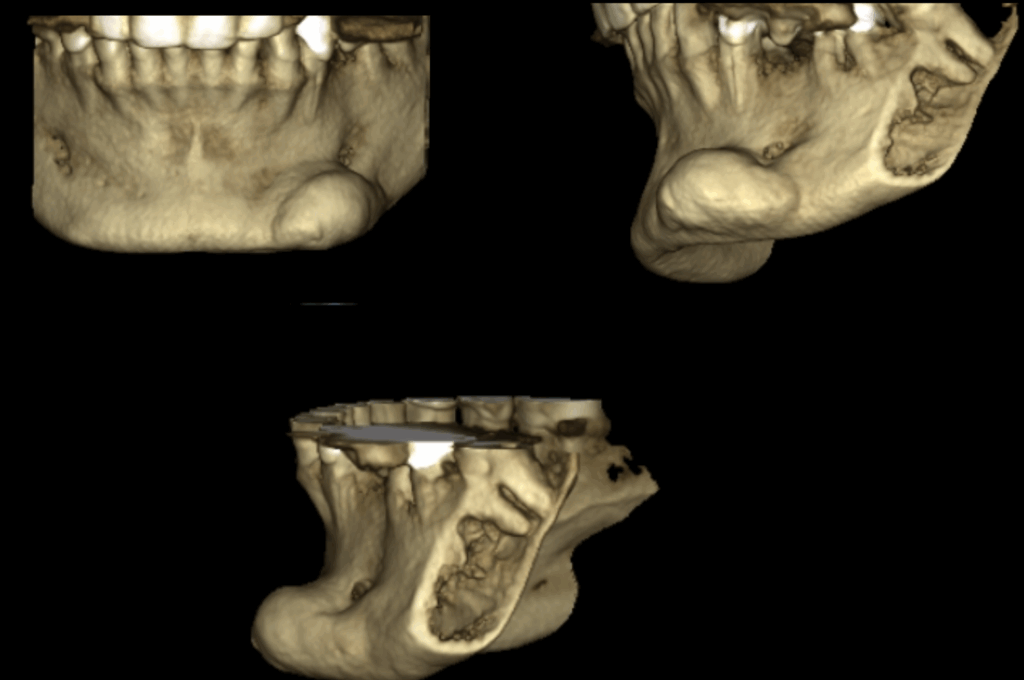

A la evaluación de la tomografía volumétrica de campo 10 x 10 se observa la presencia de la misma imagen hiperdensa a nivel mandibular del lado izquierdo y por vestibular de limites definidos y base pediculada a la altura de las piezas 33 y 34 y muy cerca al conducto dentario inferior compatible con osteoma mandibular.

RECONSTRUCCIÓN 3D